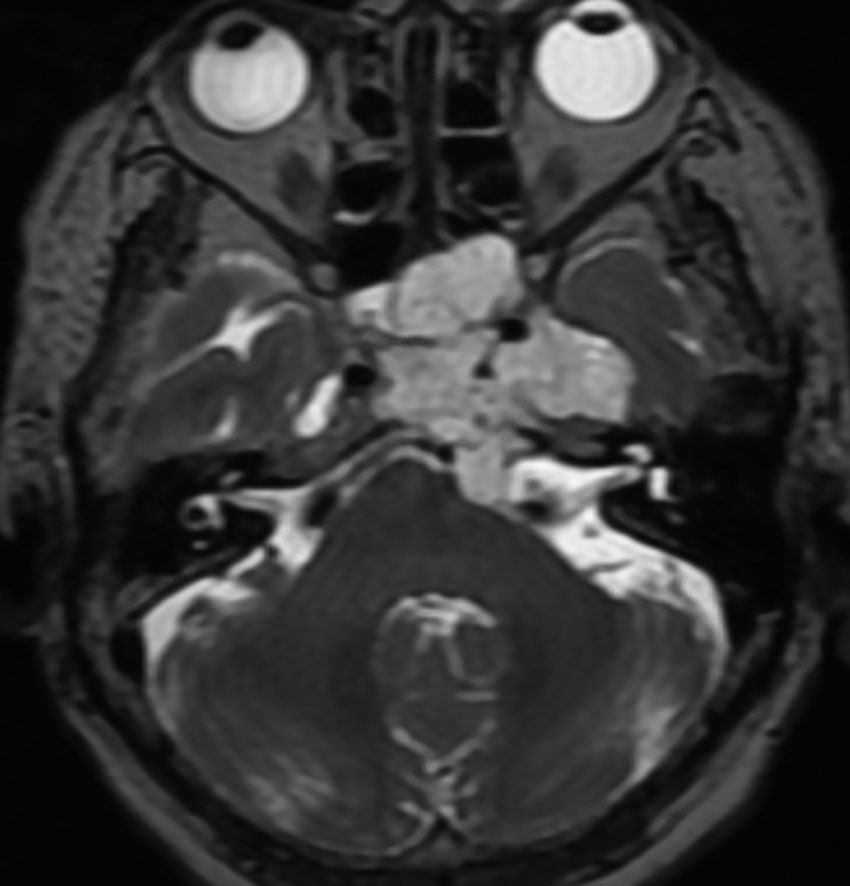

左動眼神経麻痺が急速に進行した例です。斜台から左海綿静脈洞,錐体骨尖を侵す頭蓋底軟骨肉腫です。左内頚動脈は腫瘍に取り囲まれています。

T2強調画像で高信号となるのは脊索腫と同様です。斜台後方の硬膜を破って前橋槽に伸展しています。これも脊索腫と同じような伸展浸潤形態と言えます。